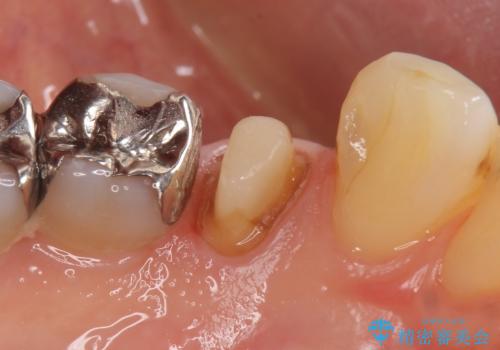

- 他院にて左下4の根管治療を行っていたが、疼くような痛みが引かないため当院にいらっしゃった方の症例です。

左下4の再根管治療を行い症状が治まったのち、オールセラミッククラウンによる補綴を行いました。